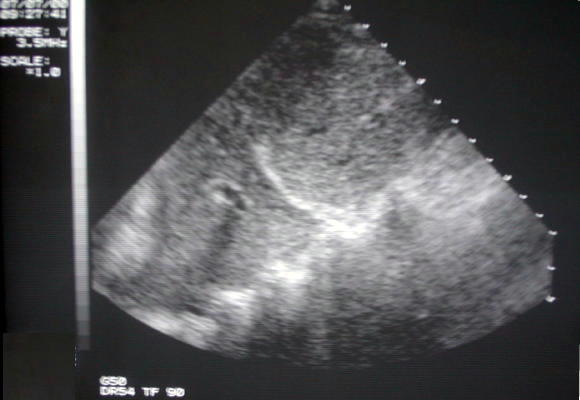

Ecosonografía Toraco - abdominal

La exploración ultrasonográfica de la base del hemitórax derecho y área abdominal superior, demuestra la presencia de zona eco lúcida refringente mixto en base pulmonar derecha, linea diafragmática interrumpida, superficie hepática de ecorefringencia normal.(Traductor....,3.5Mhrz).

Ultrasonografia base hemitorax derecho, traductor...3.5mhz